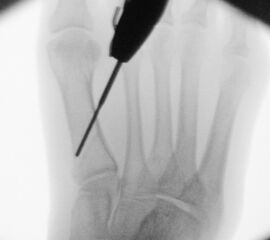

In der minimalinvasiven Fußchirurgie ist es unabdingbar, die Fräse in ihrer Position zum Knochen radiologisch zu kontrollieren, damit vulnerable Wachstumsfugen oder angrenzende Gelenke nicht verletzt werden. Zu diesem Zweck werden mit einem Bildwandler während der Operation die genaue Position der Fräse und der Osteotomieverlauf überprüft, was die Strahlenbelastung im Vergleich zu offenen Verfahren erhöht. Diese Strahlenbelastung hat potenziell einen schädigenden Einfluss auf den noch blutbildenden Knochen von Heranwachsenden. Gesicherte Landmarken am Fuß können die notwendige Zahl der Röntgenbilder und damit die Strahlung minimieren. Ist es erforderlich, mehrere Knochen zu osteotomieren, wie zum Beispiel im Bereich der Kleinzehen, werden anhand der Landmarken kleine Injektionsnadeln auf Höhe der geplanten Osteotomien vorgelegt und radiologisch im Bildwandler (BV) dokumentiert (Abb. 11). Ein solches Bild schafft eine gute Orientierung, sodass auf radiologische Kontrollen intraoperativ weitestgehend verzichtet werden kann.

Abb. 11: Lokalisation mehrerer Stichinzisionen mit einem Röntgenbild.

Zum Lesen der Bildbeschreibung und zur Vollansicht bitte das Bild anklicken. Bild: A. Helmers.